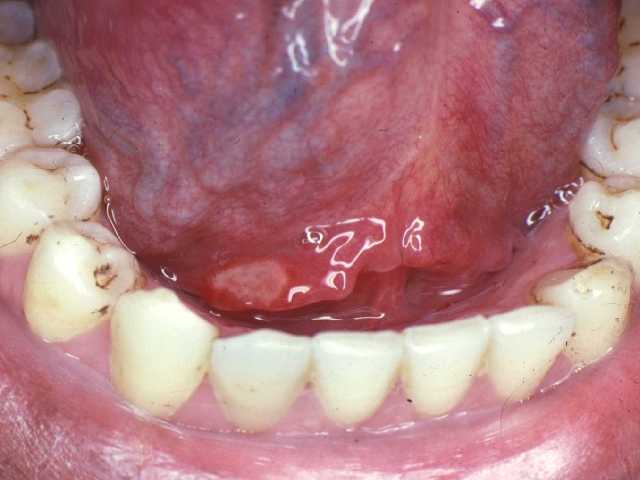

Docteur, j'ai des aphtes !

Les aphtes sont des ulcérations non spécifiques de la muqueuse buccale, dont la cause est encore aujourd’hui mal connue. On sait qu’il s’agit d’une maladie auto-immune, c’est-à-dire d’un trouble du système immunitaire, l’organisme fabriquant des anticorps contre ses propres tissus.

Dans la plupart des cas, les aphtes n’ont aucun caractère de gravité malgré les douleurs qui peuvent être très désagréables et perturbent la mastication et la phonation. Il existe cependant des formes très graves qui nécessitent des traitements lourds réservés aux services hospitaliers.

* Bouche malsaine et enflammée = gencive enflée, saignant facilement, spongieuse, sensible au toucher.

* Les ulcérations présentent un fond grisâtre, elles se couvrent souvent d’une fausse membrane, elles s’étendent en surface avec des bords irréguliers.